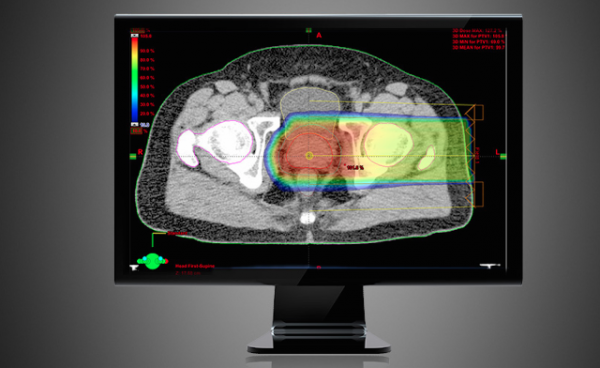

Software mostra planejamento de aplicação de radioterapia de prótons em tumores de próstata (Foto: Divulgação Varian)

Outra indicação da terapia de prótons é em áreas que já receberam radiação anteriormente. “Se esse tumor volta, não são todos os casos em que a radioterapia pode ser indicada novamente. Os tumores de próstata são exemplos disso também por uma série de condições anatômicas”, explica Pellizzon.